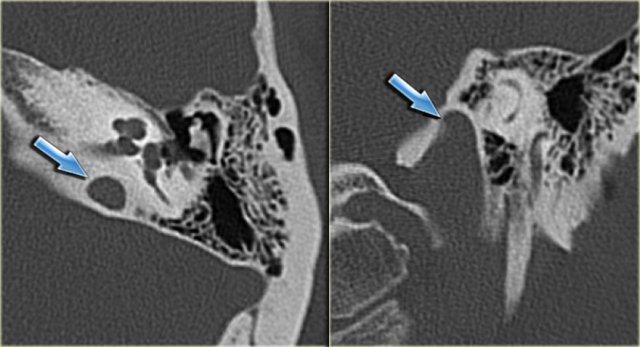

Cholesteatoma: Phụ nữ 20 tuổi với viêm tai tái phát. Mô hạt trên màng nhĩ trái. Khối mô mềm nằm giữa chuỗi xương con và thành nhĩ bên, có hình ảnh bị ăn mòn. Bên phải để so sánh.

Bên trái là hình ảnh của một phụ nữ 20 tuổi với viêm tai tái phát.

Có mô hạt trên màng nhĩ trái.

CT cho thấy một khối mô mềm nằm giữa chuỗi xương con và thành nhĩ bên, có hình ảnh bị ăn mòn.

Điều này ủng hộ chẩn đoán cholesteatoma.

Phụ nữ 20 tuổi với viêm tai tái phát. Mô hạt trên màng nhĩ trái. Khối mô mềm nằm giữa chuỗi xương con và thành nhĩ bên, có hình ảnh bị ăn mòn. Bên phải để so sánh.

Bên trái là các hình ảnh mặt phẳng coronal của cùng bệnh nhân trên.

Lưu ý cholesteatoma đã ăn mòn scutum (mũi tên).